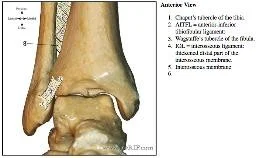

Basic Anatomy of Joints

- Types:

- Fibrous (slight movement)

- Tibio-fibular Syndesmosis